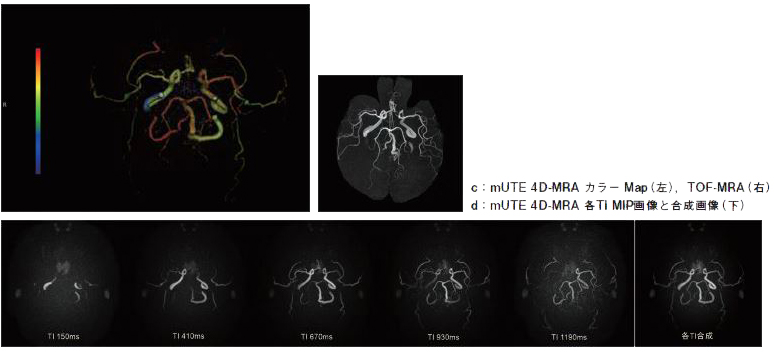

画像コメント

| a・c(左) | mUTE 4D-MRAの各TIの画像をそれぞれカラー化し、合成した画像。短いTIを青系、長いTIを赤系の色で表示した。1枚の画像で異なる流速を表示できる。 |

|---|---|

| a・c(右) | TOF-MRA。左内頚動脈の信号がやや弱く、末梢血管の信号もやや弱い。 |

| b | mUTE 4D-MRA のMIP画像TIを変化させた画像と合成画像を並べている。TIはそれぞれ150、410、670、930、1190msec。 |

| d | mUTE 4D-cの角度を変えた画像 |

頸動脈狭窄例では狭窄側の脳血流量が減少し、脳血流速度も低下する。本例も左頸動脈の狭窄と一致した左の脳血流の速度が遅くなっている。TOF-MRAではわずかな信号差となって現れているだけだが、4D-MRAでは左右の流速の差を時間軸に沿って明瞭に確認することができる。

TOF-MRAで特に内頸動脈で右側に比べ左側の信号がやや弱く、また末梢血管の描出も悪いと感じたため、左右の血流に差があると考えmUTE 4D-MRAを追加した。実際に4D-MRAでは左右で到達時間に差があり左側が遅かった。動画の他に1枚の画像で流速の違いを表すことができないかと考え、各TIの画像をそれぞれカラー化し重ね合わせを行うことでそれを試みた。なお短いTIを青系、長いTIを赤系の色で表示した。

mUTE 4D-MRAを用いて左右脳血管の到達時間をカラーマップ表示することで明瞭に描出している。今後、速度の定量化の可能性を示唆される。